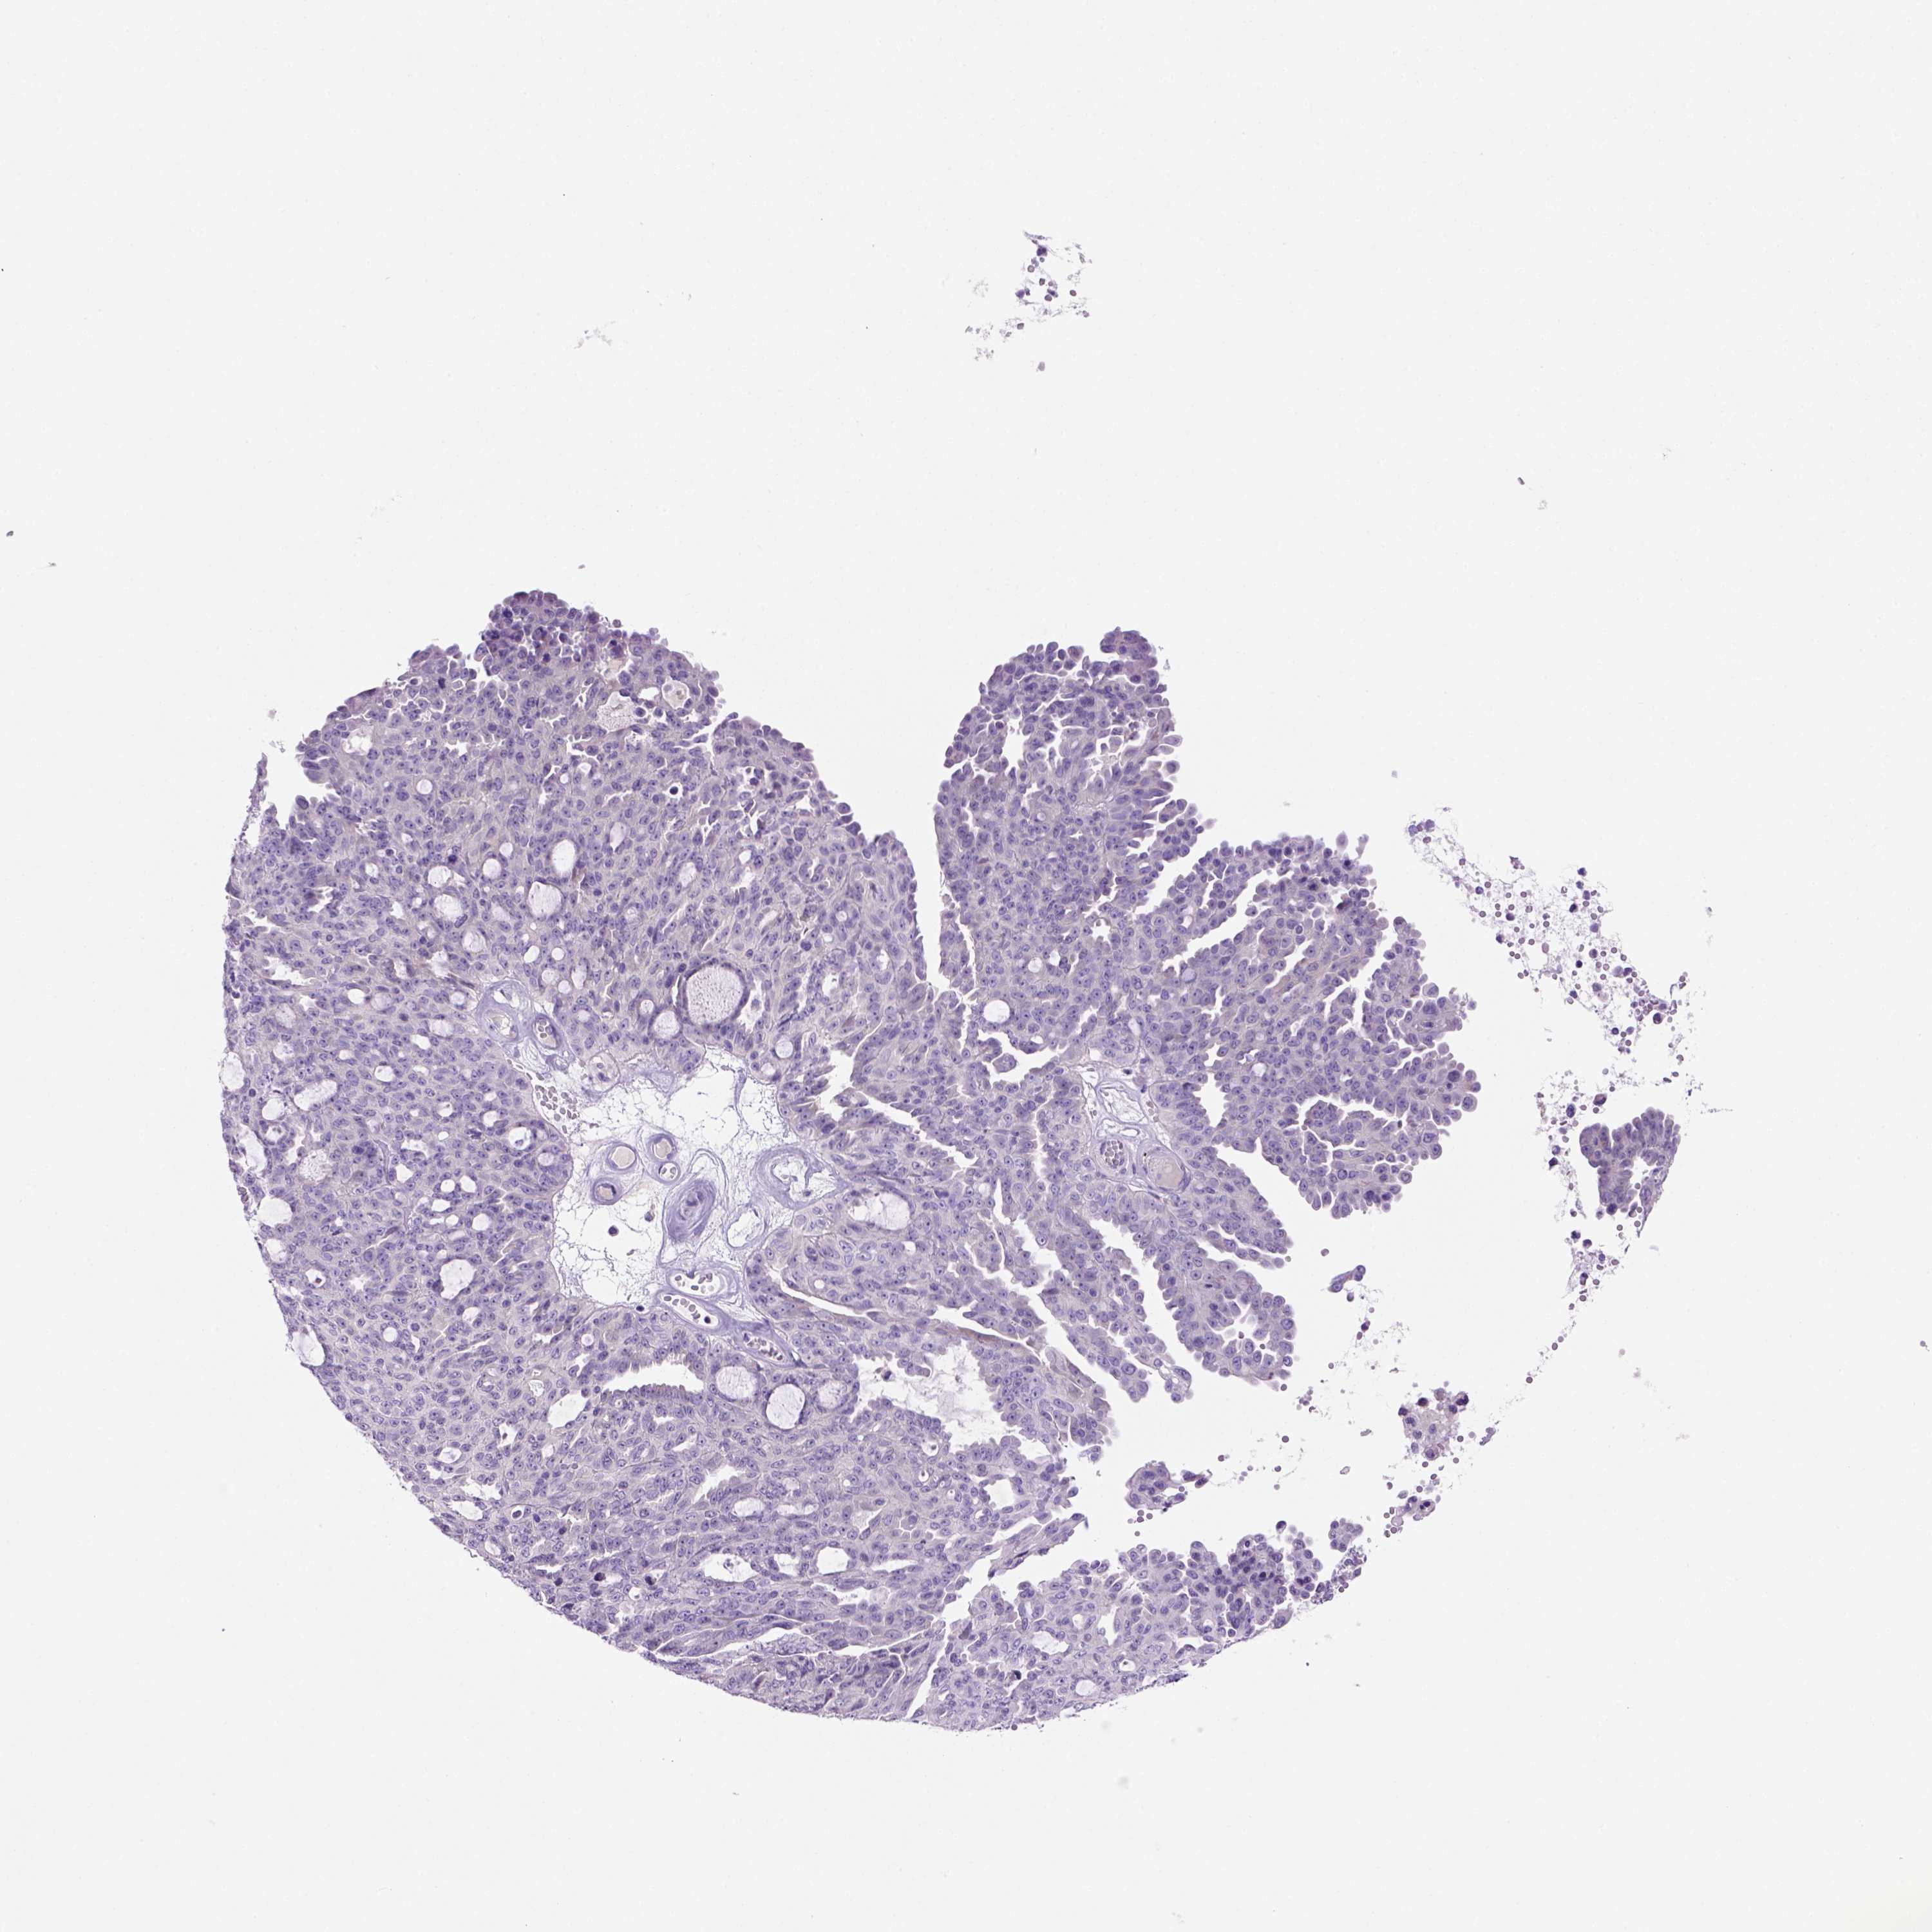

OVARIAN CANCER - Protein expressioni

A mouse-over function shows sample information and annotation data. Click on an image to view it in a full screen mode. Samples can be filtered based on level of antibody staining by selecting one or several of the following categories: high, medium, low and not detected. The assay and annotation is described here.

Note that samples used for immunohistochemistry by the Human Protein Atlas do not correspond to samples in the TCGA dataset.

Antibody stainingi

Antibody staining in the annotated cell types in the current human tissue is reported as not detected, low, medium, or high, based on conventional immunohistochemistry profiling in selected tissues. This score is based on the combination of the staining intensity and fraction of stained cells.

Each image is clickable and will lead to virtual microscopy that enables deeper exploration of all samples and also displays staining intensity scores, fraction scores and subcellular localization as well as patient and tissue information for each sample.

Antibody HPA042663

Cystadenocarcinoma, serous, NOS

Cystadenocarcinoma, mucinous, NOS

Carcinoma, endometroid